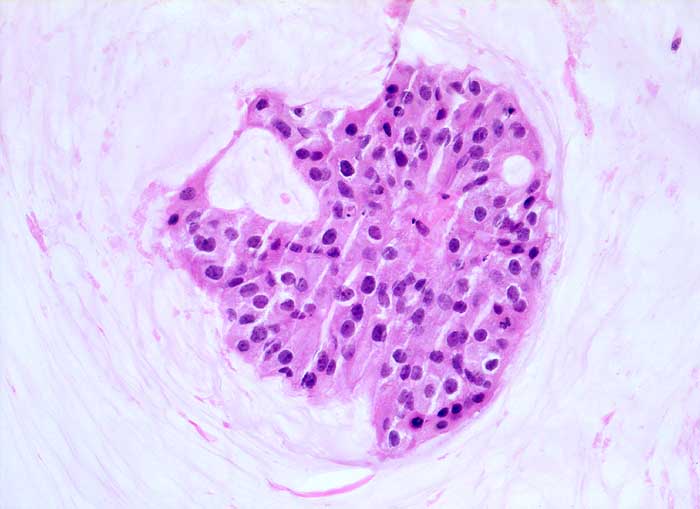

Homogene oder schlierenförmige extrazelluläre Schleimmassen mit Inseln von Tumorzellen mit geringen Kernatypien sind pathognomonisch für das muzinöse Mammakarzinom. Die Zellzahl ist meist nicht sehr hoch. Die Zellen liegen einzeln oder in kleinen kugeligen oder pseudopapillären Verbänden. Der Schleim erscheint in der Pap Färbung blau-grau bis rötlich. Siegelringkarzinome zeigen grössere intrazytoplasmatische Schleimvakuolen.

Unten werden zwei Beispiele von typischen muzinösen Karzinomen gezeigt.